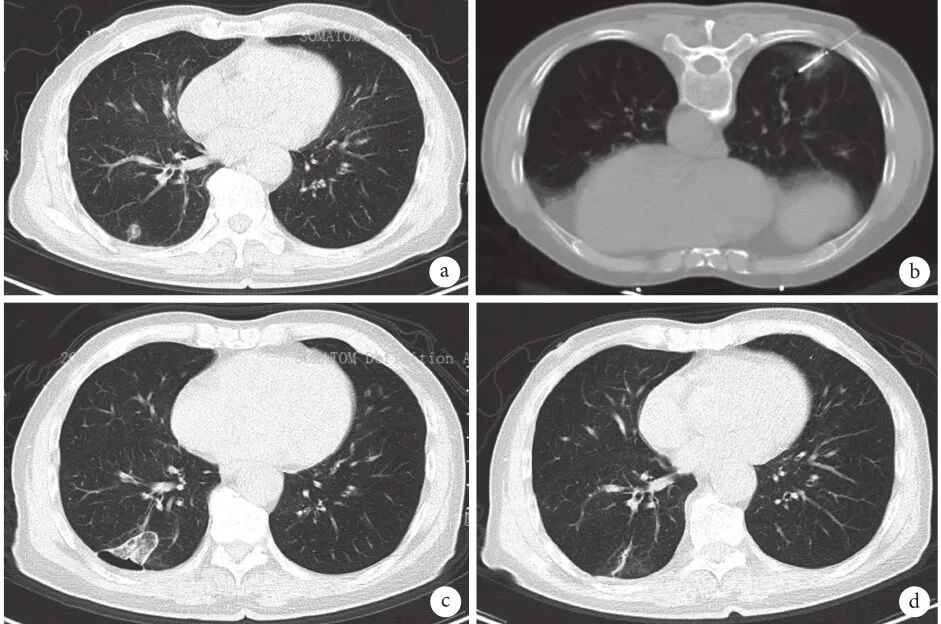

肺磨玻璃结节(ground-glass nodule,GGN)是体检或偶发早期肺癌的主要表现形式,常见于年轻、女性和不吸烟人群,正确的随访与处理策略可在降低肺癌死亡率的同时避免过度治疗。持续存在的GGN大多数为腺癌或前驱腺体病变,但呈惰性生长或长期不生长,有条件的随访是十分安全的。GGN必须采取个体化诊治策略,在充分考虑浸润程度、动态变化、治疗疗效与并发症、患者身体状况及心态等因素后做出治疗决策。不同于其它类型肺癌的尽早治疗策略,GGN型肺癌治疗时间窗很宽,必须在充分考虑治疗利弊后确定治疗时机。 外科手术是主要根治手段,对表现为GGN的前驱腺体病变目前普遍采取亚肺叶切除及不清扫淋巴结的术式。鉴于绝大多数GGN型肺癌属于无转移的局部病变,对不宜或不愿外科手术者可考虑采用介入根治。一般采用经皮微波、射频及氩氦刀等消融技术进行介入根治,具有创伤小、对肺组织损伤轻、可多次操作及可同步活检等优点,现有的研究结果已证实了消融治疗的可行性。超声与导航引导下经支气管消融治疗肺结节的疗效已初步得到了证实,是介入根治GGN的新途径。 未来在GGN的治疗上,消融治疗有望与外科手术同等重要,根据病灶特点、部位及患者情况等来选择治疗方法,以求患者利益最大化。近几年来,消融治疗 GGN 的探索逐渐增多。本文将在进一步认识 GGN 的基础上,探索 GGN 的诊治策略,并从呼吸介入角度,介绍消融治疗在 GGN 中的应用。 关键词:磨玻璃结节;诊治策略;经皮消融;根治 【正 文】 肺部磨玻璃结节(ground-glass nodule,GGN)指高分辨率CT表现为肺内边界清楚或不清楚的直径(或最大径) ≤30 mm的圆形或类圆形密度增高阴影,但病变密度不足以掩盖其中走行的血管、支气管、小叶间隔等结构,可为单发或多发,不伴有肺不张、肺门及纵隔淋巴结肿大和胸腔积液。 随着影像技术的发展、肺癌筛查的普及,GGN的检出率明显上升,因其与肺腺癌密切相关而备受关注。近年来多个国家、地区开展了肺癌筛查研究并提示,肺癌高风险人群中GGN的发病率为2.0%~3.3%。国内有报道在普通人群筛查发现的肺癌中,84.8%~95.5% 的患者在影像学上表现为GGN。与传统观念中的肺癌好发人群不同,大量研究数据显示恶性GGN好发于年轻、非吸烟、女性。 目前GGN在筛查、随访、治疗策略等方面缺乏共识,手术仍是拟诊GGN型肺癌根本的治疗策略,尽管最佳术式还存在争议。随着介入消融技术的发展,其应用范围也在不断拓宽。近几年来,消融治疗GGN的探索逐渐增多。本文将从GGN认识上的进展、诊治策略及经皮消融技术根治GGN的现状与探索等方面展开。 GGN根据是否存在实性成分可分为:纯磨玻璃结节(pure GGN,pGGN)和混合磨玻璃结节(mixed GGN,mGGN),前者又被称为无实性结节,后者又被称为部分实性结节(图1)。GGN的病理基础是肺泡间隔增厚,或部分肺泡腔充满液体、细胞或组织碎片,因此GGN并非某病的特异表现,它既可见于浸润性肺腺癌、腺体前驱病变,又可见于局灶性间质纤维化、肺泡出血、炎症或细支气管上皮增生、细支气管周上皮化生等。持续存在的GGN是指结节至少持续存在3个月以上且复查时未变小或消失。应特别重视持续存在的GGN,因其多为恶性或有向恶性发展的潜能。Kim等报道有超过80%持续存在的GGN最终被诊断为腺癌或前驱腺体病变。Lim等的研究也发现,最大径≥10 mm持续存在的pGGN手术病理100%为腺癌或前驱腺体病变。 GGN型肺癌均为腺癌,多数学者认为是经有序的多阶段发展而来的。从影像上由pGGN发展为mGGN或实性结节。在病理学上,通常是由非典型腺瘤样增生(atypical adenomatous hyperplasia,AAH)到原位腺癌(adenocarcinoma in situ,AIS),再进一步发展为微浸润腺癌(minimally invasive adenocarcinoma,MIA)、浸润性腺癌(invasive adenocarcinoma,IAC)。 GGN是一种非特异性的影像学表现,但其影像特点对于判断病理性质帮助很大,多数GGN的影像与病理存在相关性。纯磨玻璃影被认为是AAH或AIS的表现,当pGGN<5 mm时多为AAH;介于5~30 mm,AIS的可能性最大。 但值得注意的是,即便是pGGN,少数可能是MIA,极少数甚至已是IAC,其中大部分为贴壁生长型,但也有少数呈非贴壁生长型。而对于mGGN,当实性成分直径<5 mm以MIA多见,≥5 mm则提示IAC的可能性较大。GGN病灶越大,实性成分越多,其恶性可能性越大,侵袭性越强。此外,结节的形态,边缘(毛刺征、分叶征、血管集束征)及内部结构特征(CT值、空泡征、支气管充气征等)也是鉴别良恶性、侵袭性的重要影像征象。 现有的研究数据表明40%~50%的GGN在随访3~4个月时消失,这些属于暂时性GGN,考虑为良性病变。持续存在的GGN虽然多为腺癌或前驱腺体病变,但长期随访多无变化,仅少数出现生长。Chang 等报道122个pGGN随访近5年,90.2%未见生长。日本国立癌症研究中心牵头的一项多中心前瞻性研究发现,在4.3年的平均随访期内,1 046例pGGN中仅6.6%发展为mGGN。与pGGN相比,mGGN在随访中出现生长的比率较高。Sawada等的研究发现24.2%的mGGN在5年随访期内生长,远高于pGGN的12.8%;而且实性成分占比(consolidation/tumour ratio,CTR) 越高,生长的可能性越大,CTR 0.1~0.25、0.26~0.5、>0.5的mGGN随访5年的生长率分别为14.2%、28.6%、30.8%。GGN即使生长也呈惰性缓慢生长,倍增时间很长。根据研究报道mGGN的倍增时间是457~568 d,pGGN更是长达469~845 d。有研究数据表明,GGN的生长绝大多数发生在3~5年内。有一项研究报道CTR<0.5的108个GGN,平均随访4.2年,26.9%在随访期内增大,且均在随访3年内出现。Lee等报道了351个GGN随访10年的研究数据,发现后5年的GGN生长率不及前5年的1/3。对GGN生长规律的了解,有助于我们做出正确的处理策略,避免过度诊治。 如前所述,持续存在的GGN多数为腺癌或前驱腺体病变,根据影像特点是无法排除恶性病变的。因此,高分辨率CT发现GGN后如果3个月随访无缩小或消失就需要进行长期随访,直至可排除恶性。GGN生长缓慢或长期无改变,故随访期限一般至少5年。随访时间间隔应根据恶性风险及可能的浸润程度、患者的具体情况而定。 目前在国内外有许多相关的指南、共识,但由于各指南、共识制定者的专业背景、地域以及针对人群的不同,推荐的GGN随访策略差异较大。其中几个主要指南、共识的随访策略归纳见表1。指南及共识的策略差异导致了临床医生的困扰,但在临床工作中这些指南、共识只能提供参考,在对GGN的具体处理上应针对不同患者、病灶制定个体化的随访策略。 表1 国内外主要指南、共识对磨玻璃结节随访及处理的建议总结 我们结合长期的临床经验,提出以下几点供参考: GGN初次发现后均应3个月随访,大多数良性GGN会有缩小或消失; 首次随访无变化者应根据影像特征评估恶性风险及可能的病理类型,可疑AAH者可年度或2年后随访,可疑AIS者可6~12个月后随访,可疑MIA者 3~6个月后随访,可疑IAC者 3个月后随访或考虑活检、治疗; 后续随访时间间隔根据前一次随访评估的病理类型确定,在动态随访中如出现结节增大、实性成分增加或新出现恶性征象应缩短随访间隔或进行活检、治疗,如病灶持续稳定,可适当延长随访间隔时间; 必须结合患者身体状况及心态等因素来确定GGN的随访策略。对于预计生存期有限的高龄、合并严重慢性疾病患者,随访不宜过于积极,甚至可长期不随访;对于心态十分焦虑的患者,随访应相对积极。 GGN密度较低且存在正常的肺内血管,与实性结节相比非手术活检确诊率相对较低、出血风险较大,同时对恶性的浸润程度判断也欠准确。然而,非手术活检仍是GGN除外科手术以外唯一的确诊手段,具有明确病变性质以便对因治疗、避免外科误切、缓解患者心理压力等作用。因此,严格筛选非手术活检的适应人群及充分掌握活检技术也是GGN诊治策略的重要一环。 GGN非手术活检的主要适应证包括:有典型恶性特征但不愿或不宜外科手术、疑诊为可经内科治愈但病因不明的良性疾病、同时存在类似的多发结节且不能排除恶性;且均必须通过评估确认非手术活检可取到合格标本。活检途径分为经皮及经支气管两种,前者宜用于无支气管相通、活检部位无明显血管的病灶,后者则主要用于与支气管管腔相通的结节病灶。经皮穿刺活检是肺结节诊断的传统有效技术,报道的GGN诊断率约64.6%~93%。对≤1 cm的GGN确诊率差别更大,48.5%~87%不等。近来,经引导鞘管超声支气管镜(endobronchial ultRASonography with a guide sheath,EBUS-GS)及导航技术的应用,大大提高了GGN经支气管活检的确诊率及安全性,其阳性率达到57%~69%,病灶越大阳性率越高,而且高分辨率CT可见支气管与病灶中间相通者确诊率更高。冷冻活检能够取到较大的标本,有望明显提高诊断率。有研究[49]报道EBUS-GS联合超细探头冷冻肺活检诊断率可达到82.61%,且诊断率与病灶大小、CTR、是否采用导航或X线透视等因素无关,值得进一步探索。 除非高度怀疑真菌感染或浸润性肺癌,一般需在随访3个月以上才考虑活检,以避免不必要的活检。 GGN病灶及其周围存在正常肺部血管,经皮穿刺活检进针及活检切割时必须尽量回避较大血管,防止大出血。 pGGN经皮穿刺活检阳性率较低且出血风险大,必须慎用。 如病灶部位血管丰富,于微波或射频热消融中或消融后进行经皮穿刺活检可减少出血量、提高安全性,且不影响活检的病理检查结果。 为提高诊断率及减少并发症,经支气管镜活检应该在超声探头可探及病灶的前提下进行,冷冻肺活检最好在X线实时透视下采用细探头取材。 外科手术切除是拟诊恶性GGN的主要治疗方法。《上海市肺科医院磨玻璃结节早期肺腺癌的诊疗共识(第一版)》中对可疑AIS、MIA及IAC的GGN的手术指征做了较为详细的说明,但病理类型仅通过影像特征分析得出,存在不准确的可能性。 目前相对比较一致的观点是当多学科会诊后高度怀疑IAC病变时,应手术干预。对于影像特征怀疑为AIS或MIA时,需要根据病变部位、随访时间长短、发展为浸润病变的概率等因素综合考虑。GGN型肺癌是一种惰性的肿瘤,有条件随访十分安全,治疗窗口期很长。因此,对前驱腺体病变不应过早积极手术干预,以避免过度治疗。另外,是否考虑手术治疗必须结合病灶部位、结节数量、患者的预计生存期及心态等,对于非优势部位、双侧多发、高龄或有严重基础疾病者手术宜消极,反之则可积极考虑手术治疗,当患者对GGN十分焦虑时手术指征也可适当放宽。 随着临床研究的深入,临床医生对GGN的切除范围有了更准确的认识。基于1995年的一项随机对照研究(RCT),肺叶切除被认为是早期肺癌的标准术式。然而对于肺结节病灶,尤其是近几年来备受关注的GGN型肺癌,最佳的切除范围还存在争议。切除范围的选择,需要综合考虑病灶影像特征及部位、患者年龄及心肺功能等因素。日本的Ⅱ期临床研究JCOG0804/WJOG4507显示,对最大径≤2 cm,CTR≤0.25的GGN型肺癌进行足够切缘的亚肺叶切除,5年无复发生存率达99.7%。美国国立综合癌症网络(NCCN)指南已推荐亚肺叶切除可用于最大径≤2 cm,CTR<0.5的外周GGN(2类)。而对于CTR>0.5的病灶,其术式的选择仍存在争议。参考NCCN指南的建议,对于CTR>0.5的mGGN,在患者可耐受的情况下仍优先考虑肺叶切除。但近年来国内外开展了一些研究,试图探索这部分患者的最佳术式,也提出了新的观点。国内有临床研究报道,CTR>0.5的mGGN行肺段切除与肺叶切除的5年无复发生存时间相仿。 另有两项针对直径≤2 cm mGGN的RCT正在进行(日本的JCOG0802和美国的CALGB140503),从JCOG0802已报告的部分研究结果来看,对于最大径≤2 cm、CTR>0.5的mGGN,肺段切除无论是总生存率还是肺功能保留方面都优于肺叶切除,但还需待其最终研究报道。尽管如此,目前支持亚肺叶切除用于CTR>0.5 的mGGN的证据尚不足,有待进一步研究。除了病灶大小、CTR外,术中冰冻病理可以辅助GGO病灶的术式选择。有一项纳入803例Ⅰ期肺腺癌患者的研究发现,术中冰冻病理判断AIS、MIA、IAC的准确率可到达96%。对于术中病理为AIS、MIA的GGN行亚肺叶切除,5年无复发生存率达100%。 为达到术中创伤最小化及术后生存期最大化的目的,外科学者也在不断探索GGN型肺癌术中淋巴结的处理方式。多项研究结果提示GGN的淋巴结转移率很低,pGGN的淋巴结转移率为0,CTR<0.5的mGGN其淋巴结转移率0~6.9%。Moon等的研究提示肿瘤大小和CTR是淋巴结转移的独立预测因素。一项纳入129例CTR<0.5的GGN患者的回顾性研究发现,无论是否进行淋巴清扫、采样,患者的5年无复发生存率无差异。还有类似的研究也提示,对于CTR<0.5的GGN,淋巴结清扫与否并未影响患者的预后。根据2021年NCCN指南的建议,对于最大径<2 cm,CTR<0.5的外周GGN,技术允许情况下需进行N1、N2淋巴结采样。而对直径>2 cm或CTR>0.5的GGN,目前更为推荐系统性淋巴结清扫。此外,术中冰冻病理也是淋巴结处理方式的重要参考指标。有研究结果提示,对于术中冰冻病理为AIS及MIA未进行淋巴结清扫,其5年无复发生存率可达100%。考虑到AIS及MIA不发生淋巴结转移,《上海市肺科医院磨玻璃结节早期肺腺癌的诊疗共识(第一版)》指出,对于影像拟诊AIS或术中冰冻初步诊断为MIA,不需要进行淋巴结清扫或采样。基于目前的研究结果,我们认为在进行术式选择时不能一概而论,要充分考虑GGN的大小、形态、位置、CTR等因素,参考术中冰冻病理结果,选择可根治、创伤小、尽量保留肺功能的术式。 除了外科手术,立体定向体部放疗(stereotactic body radiation therapy,SBRT)及消融技术介入治疗也是肺结节的治疗手段。SBRT可用于经多学科联合诊疗认为不能耐受外科手术的早期肺癌。然而,GGN病灶存在剂量传递及实时影像引导难以实行等问题,关于SBRT治疗GGN的研究甚少。有项单臂回顾性研究提示SBRT治疗GGN型肺癌可获得较好的局部控制。另外还有少数SBRT治疗早期肺癌的研究中包含少量GGN病灶,提示磨玻璃病灶与更好的预后相关。但目前缺乏足够的证据支持SBRT用于拟诊GGN型肺癌的治疗。 肺癌的经皮介入治疗技术主要包括热消融如射频消融(radiofrequency ablation,RFA)、微波消融(microwave ablation,MWA),冷冻消融如氩氦刀冷冻消融(argon-helium cryoablation,AHC)以及放射性粒子植入等,目前临床常用于早期肺癌的消融技术是经皮RFA、MWA 、AHC等。 RFA是目前治疗实体瘤最为广泛的消融技术,也是应用于肺部肿瘤最早,经验最丰富的消融治疗手段。消融体积主要取决于局部射频产生的热传导与血液及细胞外液间的热对流,但其热沉效应明显,易受组织特性影响。在肺部,RFA主要适用于小到中等大的肺癌。近年来,RFA用于治疗不能耐受或拒绝手术的Ⅰ期肺癌的报道越来越多,结果提示其无复发生存或总生存与手术或SBRT相当。研究还显示RFA治疗早期肺癌的5年无进展生存率为40%~74%,而肿瘤大小是其预后的重要影响因素,<3 cm的肿瘤预后更佳。2013年美国胸科医师学会(ACCP)推荐RFA用于<3 cm且不适合手术的外周型Ⅰ期非小细胞肺癌。 MWA是将微波消融针(微波天线)穿刺到靶组织内产生微波能量,使肿瘤细胞凝固坏死。MWA具有肺内对流性更高、热沉效应更弱的特点,其消融范围较RFA大,而且所需的消融时间更短,耐受性更好。理论上MWA相较于RFA可能获得更好的肿瘤局部控制。近10年来,MWA治疗早期肺癌的研究也逐渐增多。一项纳入104例Ⅰ期非小细胞肺癌的研究发现,MWA治疗后的局部复发率为23%(中位随访时间47个月),而肿瘤>3.5 cm是局部复发的独立危险因素。而且该研究还对复发者再次进行MWA,这些患者与未复发者的生存结局相仿。该研究给了我们两点启发:首先是严格控制消融治疗的肿瘤大小,可以获得更好的局部无复发生存;其次是复发者可重复MWA治疗,其预后与未复发者一样。Han等的研究发现MWA治疗75岁以上早期肺癌患者的4年肿瘤特异性生存率为64.7%。一项2019年的多中心回顾性研究则发现,MWA治疗80岁以上老年早期肺癌患者的5年局部控制率为63.9%。Wang等的对照研究进一步发现,肺叶切除与MWA治疗的2年无疾病生存率分别是75.29%和76.09%,尽管在该研究中两种治疗的预后相仿,但MWA的治疗花费明显低于肺叶切除。 AHC是通过高压氩气使组织迅速降温至–140℃,再通过氦气使组织升温到20℃~40℃,温度变化使得靶组织蛋白质变性、细胞裂解、组织缺血坏死等。AHC可以达到与MWA相当的消融范围,而且具有更好的保留细胞结构、对周围组织损伤小、操作过程中可清晰观察到消融边界等优点,其主要的缺点是操作时间相对较长。同RFA及MWA一样,AHC也推荐用于3 cm以内病灶的消融治疗。近年来关于冷冻治疗早期肺癌的研究也逐渐兴起。Yamauchi等对22例接受AHC治疗Ⅰ期肺癌患者进行回顾性研究,发现随访期内仅3%病灶出现进展,平均无进展时间为(69±2)个月,3年无疾病生存率67%。Moore等的研究结果显示AHC治疗Ⅰ期非小细胞肺癌的5年无进展生存率可达87.9%±9%。Zemlyak等的研究则对比了亚肺叶切除、RFA及AHC治疗早期肺癌的疗效,结果显示亚叶肺切除与AHC的3年肿瘤特异性生存率分别是90.6%和90.2%。以上研究提示经皮AHC治疗早期肺癌的局部复发率低,总生存率与亚肺叶切除相当。 目前,关于经皮消融治疗早期肺癌的研究越来越多,而且大多取得不亚于手术切除或SBRT的疗效。值得注意的是,在手术仍是早期肺癌主流治疗的大环境下,消融治疗的作用可能被低估。因为接受局部消融治疗的患者往往年龄更大、肺功能更差、体力活动状态(PS)评分更高。而这是消融治疗面临的普遍问题。一项单中心的回顾性研究较清晰地阐明了这种情况,该研究回顾性对比RFA、SBRT及亚肺叶切除治疗Ⅰ期肺癌患者的5年总生存率和无进展生存率,结果分别是RFA 58.9%和39.3%、SBRT 42.0%和34.9%、亚肺叶切除 85.5%和75.9%,而这明显的差距却在矫正了PS评分等因素后消失了。 GGN能否通过消融治疗达到根治?要回答这个问题需要明确以下两点:GGN型肺癌是否存在转移、能否当作局部疾病进行治疗?消融技术介入治疗GGN病灶能否达到根治? 有关GGN型肺癌的转移问题关键要看是否存在淋巴结转移,相关的研究数据报道较多。Zha等的一项纳入867例GGN型肺癌的研究显示,pGGN、CTR<0.5 mGGN、CTR 0.5~0.79 mGGN的淋巴结转移率分别为0%、6.9%、9.1%。而在Ye等的研究中,淋巴结转移率 pGGN为 0%、mGGN为 2.2%,均远低于实性结节的27%。一项回顾性研究纳入了581例GGN型肺癌,其中145例CTR≤0.5、最大径≤3 cm的GGN均未见淋巴结转移,而且该研究中27例0.5<CTR<1.0、最大径≤1 cm的GGN型肺癌也未见淋巴结转移。综合大量的研究数据可发现,pGGN均未见淋巴结转移,CTR≤0.5或最大径<1 cm的mGGN淋巴结转移率极低,而CTR>0.5或最大径>1 cm的mGGN淋巴结转移率也明显低于实性结节。从病理角度,AIS和MIA阶段没有淋巴结转移,即便是IAC,如果CTR≤0.5也极少有淋巴结转移。另外,GGN型肺癌未见远处转移的报道,不少专家提出GGN型肺癌无需行头颅磁共振成像(MRI)、骨扫描、支气管镜等检查评估。综上,绝大多数GGN型肺癌属于无转移的、可经局部治疗治愈的局部病变,提示局部消融治疗有根治该类疾病的可能性。 那么,消融治疗GGN病灶能否达到根治呢?消融治疗在早期肺癌中的成功应用,也促进了它在这一特殊类型早期肺癌中的探索。GGN型肺癌属于3 cm以内早期肺癌或原位癌,理论上看可根治实性早期肺癌的消融技术也完全有可能根治GGN型肺癌。尽管目前消融技术根治GGN的报道并不多,但均取得了令人满意的结果。Kodama等的回顾性研究发现,接受RFA治疗的42例GGN型肺癌患者中位随访时间42个月,5年总生存率和肿瘤特异性生存率分别为96.4%和100%。Iguchi等纳入16例GGN型肺癌患者进行RFA治疗,中位随访时间61.5个月,3年的病灶控制率达92.3%,且未发现严重并发症。我国的一项回顾性研究也观察到了RFA治疗GGN型肺癌的近期疗效,半年的病灶控制率100%。2018年一项回顾性多中心研究纳入了51例接受MWA治疗的GGN型肺腺癌患者,技术成功率100%,3年无局部进展生存为98%,3年肿瘤特异性生存率为96%,并发症均在可控范围。2020年也有一项回顾性研究报道了MWA在多发GGN中的应用,技术成功率100%,中位随访18个月未发现肿瘤复发,但该研究随访时间较短。2015年Kim等报道了1例AHC治疗5 mm pGGN的成功病例。2019年有一项小样本回顾性研究[101]纳入14例接受AHC治疗的GGN型肺癌,结果显示随访2年未见复发且无严重并发症。 以上研究结果为消融治疗GGN提供了初步的循证医学证据,提示通过消融技术介入根治GGN型肺癌是可行的,且操作安全。需要指出的是,这些临床研究的随访时间相对较短,病例数较少,尚缺乏大样本、前瞻性临床研究的数据。相信未来会有更多大样本、多中心、前瞻性、长随访的研究,以提供高级别循证医学证据。而且,虽然消融治疗有根治大部分GGN型肺癌的可能,但其无法进行淋巴结清扫或治疗,所以并不意味着消融治疗可以替代外科手术。本中心也对一些符合条件的GGN型肺癌病例进行了经皮消融治疗,积累了一定的经验,在临床中验证了GGN介入根治的可行性,典型病例见图2~4。 图3 CT引导经皮射频消融治疗磨玻璃结节典型病例 男,78岁,右肺下叶GGN经皮穿刺活检确诊腺癌,肾功能不全不宜外科手术;a:治疗前右肺下叶1.0 cm的mGGN;b:单极射频消融治疗GGN;c:射频消融治疗1个月后影像表现;d:射频消融治疗35个月后病灶仅残留纤维条索影 女,31岁,两肺多发GGN,右肺上叶mGGN经支气管镜活检确诊为腺癌,拒绝手术;a:治疗前右肺上叶1.6 cm的mGGN;b:氩氦刀冷冻消融治疗;c:冷冻治疗10 d后影像表现;d:氩氦刀术后18个月病灶吸收仅残留少许纤维条索影 作为外科手术的有力补充,消融技术介入根治的临床应用适应证有哪些?目前尚未发布针对GGN介入根治的临床指南,仅有国内今年发布的专家共识。该共识提出的GGN消融治疗适应证可供临床应用时参考,包括: 病理证实为AAH、AIS、MIA、IAC(排除远处转移)的周围型GGN,且存在因心肺功能差或高龄等因素无法耐受手术、术后出现新病灶无法耐受再次手术、拒绝手术、多发GGN、重度焦虑等; 拒绝活检及手术的患者如有影像学恶性征象或极度焦虑,在多学科会诊的基础上与患者共同决策确定是否“可不取病理直接消融或消融与活检同步进行。”总之,鉴于目前尚缺乏高级别循证医学证据及权威指南的推荐,消融治疗应严格掌握适应证,只针对不能耐受或不愿意外科手术的患者,作为外科手术的补充。 我们结合10余年来经皮介入消融的经验,提出以下补充建议: GGN的非手术活检不能准确判断肿瘤的浸润程度,活检的病理分型只能作参考,但一般不会影响适应证的选择。 无病理确诊GGN的消融治疗适应证除了拒绝活检及手术外,还应包括经评估非手术活检难以取到合格标本或出血风险大的患者,如1 cm以内的pGGN、中间有大血管的GGN等。 选择消融治疗时必须先评估病灶所在位置对消融疗效的影响,为确保根治,病灶必须位于治疗针易于到达且周围无心脏、大血管的部位。 不能耐受手术主要包括高龄或有严重并存病、多发结节、近肺门区结节等,注意不宜手术是相对的,外科、内科、介入科医生的看法可能存在较大的差异;不愿意手术必须以经充分说明后患者及家属仍签字拒绝手术为准。 对病理未确诊的GGN,考虑到pGGN活检的病理结果准确性较差且活检后出血较明显,宜不取病理直接消融;消融同步活检主要应用于病理未确诊的mGGN,活检可在消融前、消融中或消融后进行。对血管丰富的病灶,建议采用热消融如微波或射频,且消融中进行活检为佳,有助于减少活检后出血且不影响活检的病理结果;不建议在消融后活检,因有学者提出热消融造成的组织碳化可能会影响活检的病理检查结果。消融后活检主要应用于冷冻消融时,因冷冻不会影响活检标本的病理结果。 与外科手术一样,确定消融治疗的时机需要充分考虑GGN生长规律及侵袭性。GGN型肺癌呈惰性生长,治疗时间窗很宽,为避免过度治疗,必须是经过一段时间的随访后高度怀疑为浸润性病变、或随访中病灶增大或实性成分增多时才考虑消融介入根治。另外,对十分焦虑的患者在考虑消融治疗时可积极些,对预计生存期有限的高龄或有严重并存病患者,必须在充分衡量得失后确定是否消融。消融介入治疗能否达到根治,也与操作者的操作技术及临床经验密切相关。建议MWA、RFA采取低功率、较长时间的治疗策略,确保消融后磨玻璃影大于病灶10 mm以上;氩氦刀冷冻治疗尽量采用多针适型,分2~3个循环、冷冻总时间不短于30 min,确保冷冻消融治疗中病灶位于–40℃范围内。 相较于外科手术,经皮消融介入根治GGN具有操作快速、创伤小、安全性高、费用低,对肺组织损伤轻、可多次操作,对无病理诊断者可同步活检等优点。但也存在对操作技术要求高、消融治疗参数个体差异大、质量控制要求高、较难同质化、不能百分之百确保根治等缺点。目前经皮消融根治GGN是可行的,临床主要用于不宜或不愿手术的GGN型早期肺腺癌或病理未确诊但高危的GGN。鉴于pGGN及绝大多数mGGN属于没有转移的局部疾病,未来经皮消融治疗有望成为这类患者除了外科手术以外的主要治疗手段,根据病灶特点、病灶部位及患者情况等个体化选择治疗方法。 此外,气道内超声及电磁、虚拟导航技术的快速发展使经支气管消融治疗GGN成为可能。近年来,导航技术及超声引导下插入RFA、MWA软性探头消融治疗恶性肺结节已在不断探索中,带有水微循环的经支气管镜软性消融探头也已研发成功,拓展了消融治疗范围。目前为数不多的单中心小样本的研究也初步证实了支气管镜下消融疗效确切。但该技术仍存在许多问题: 消融探头难以经病灶中间到达病灶远端,消融范围难以确保超过病灶边缘10 mm以上。 探头只能经支气管到达病灶,只能应用于消融探头能够到达的与支气管相通的病灶;支气管镜下经肺实质结节抵达术(BTPNA)可使消融电极不经支气管到达病灶部位,但该技术存在操作难度大、创伤较大、费用高、费时长等缺点。 消融治疗功率不稳定,且没有标准的消融治疗参数可供参考,影响了消融效果及该技术的普及。 设备昂贵、消融探头没有取得管理部门批准,目前只能临床科研中应用。总之,作为肺结节消融治疗的新技术,经支气管消融技术目前可探索性的应用于治疗肺功能差、经皮穿刺气胸或出血风险大的恶性GGN或实性结节。随着治疗探头更加精细、输出功率更加稳定以及BTPNA的改进、应用经验的累积,该技术将逐渐成熟,有望扩大适应证及提高根治的可能性。 一、磨玻璃结节再认识